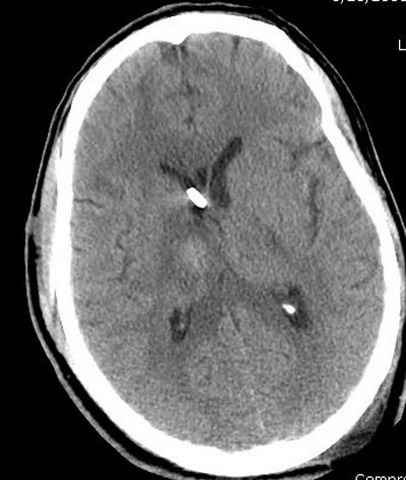

больному 42, автоавария, политравма, открытая черепномозговая травма, безсознании, открытый перелом бедра, размозжение мягких тканей, дефект кожи на передней поверхности бедра около 13 см2 от ожога, компартмент синдром.

Наблюдается службой травмы и нейрохирургии (ICP) Increased Intracranial Pressure by ventricular cateter